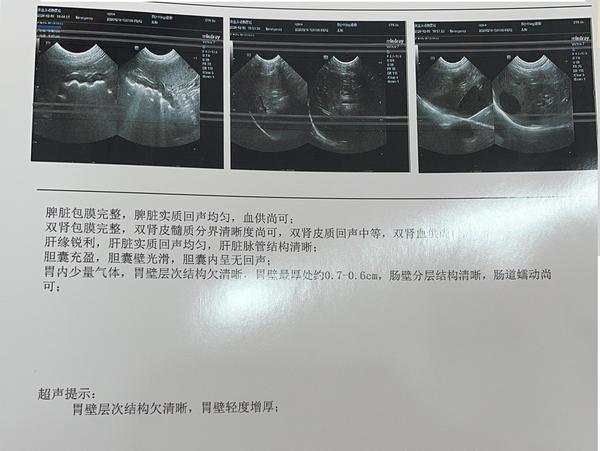

到医院后医院没有仔细看资料,开了7个检查“生化、血常规、4张X光、1组B超、胰腺炎测试、C反、粪便化验”,就是不肯做胃镜检查。宠物主人不好意思反对医生的意见所以7个化验花了2000元。化验结果和我们预料的一样,每一个都没有问题,甚至可以说狗的身体结果是完美的,血常规和生化里没有任何一项指标高或者低(健康狗里都很少),其中2张片子还是照心脏的。

过去半年主人带狗做过多次生化,血常规、粪便检查,有的医院说肠胃菌落失调,有的没有结果。我们经过对化验单的分析,和症状表现按出血型肠胃炎(不是肠胃炎出血)治疗,治疗后最近都没有拉血表现 ,但是14-15天一次的呕吐还是无法找到原因。另外出血型肠胃炎是很少见的疾病,成因目前医学上还未知,根据分析我们认为最大可能是在胃部,担心会出现肿瘤或者未来有溃疡引起的穿孔,所以我们说服宠物主人给狗在当地比较好的医院做一次胃镜确定问题出在那里,在北京大概1000元所以我们认为费用在可以接受范围里。